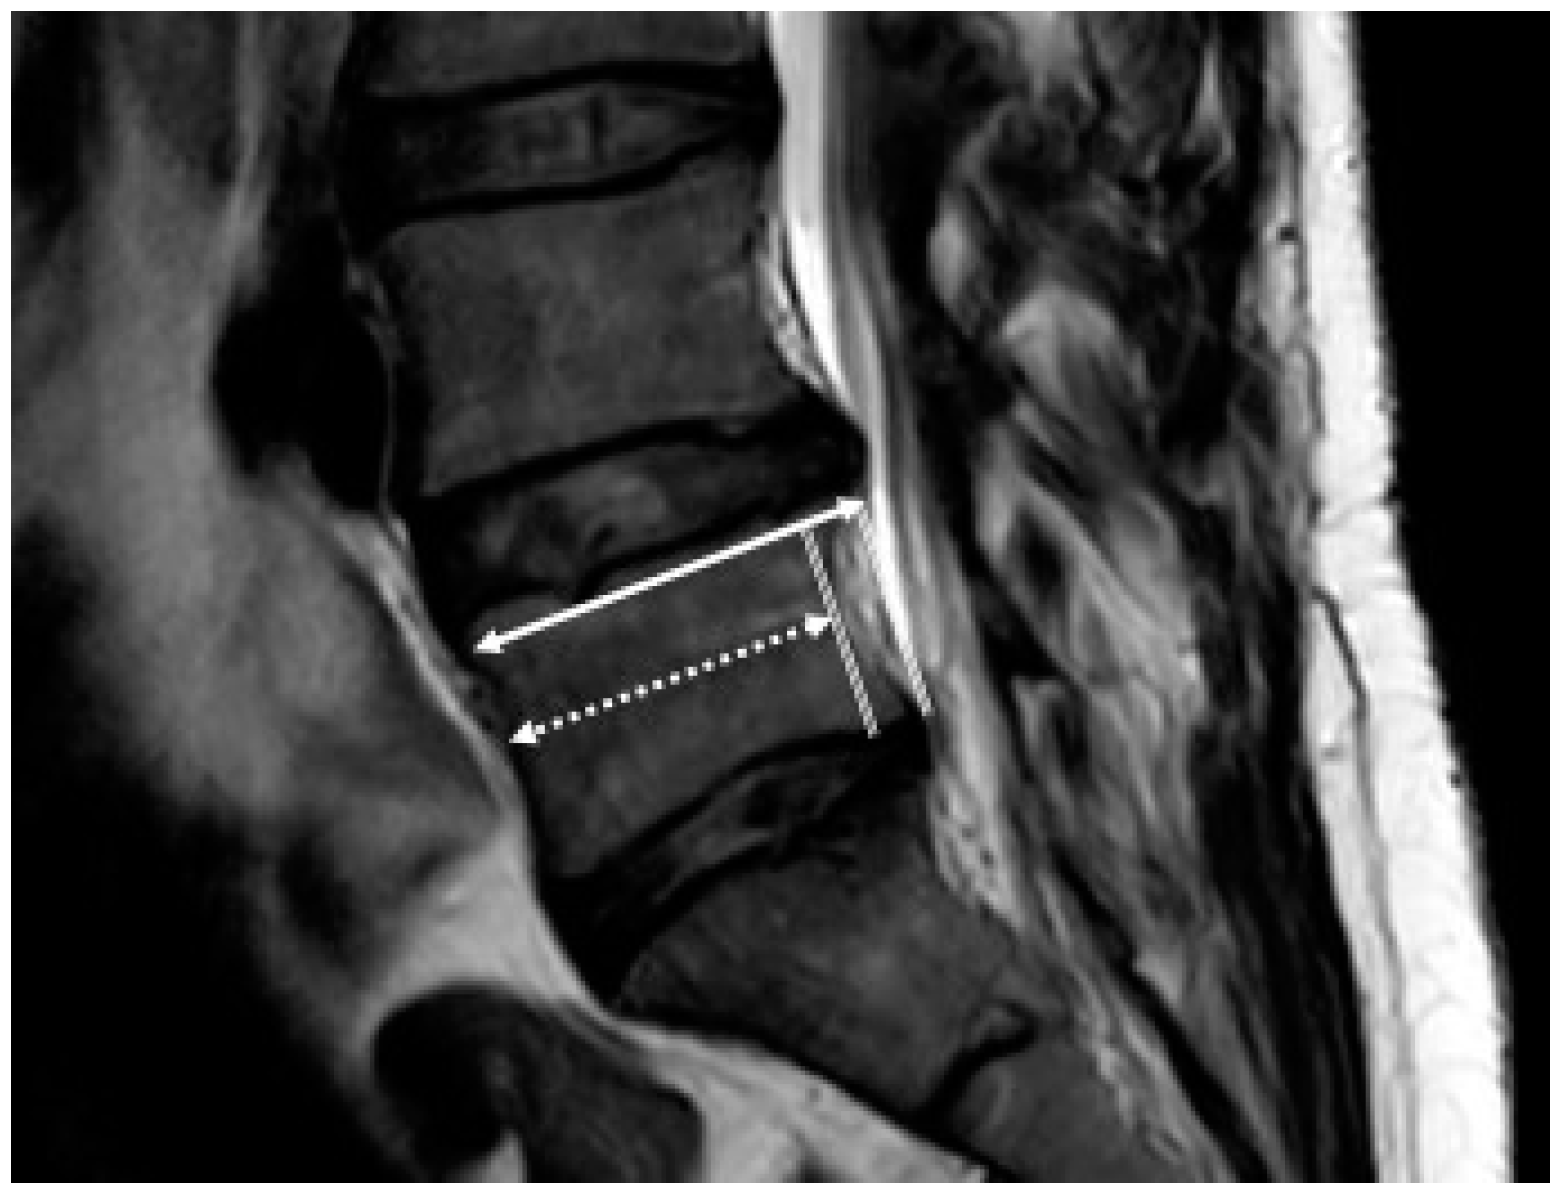

2.6. Measurement

2.7. Theory/Calculations